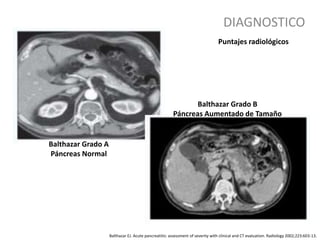

Balthazar EJ. Acute pancreatitis: assessment of severity with clinical and CT evaluation. Radiology 2002;223:603-13.

Puntajes radiológicos

Balthazar Grado A

Páncreas Normal

Balthazar Grado B

Páncreas Aumentado de Tamaño